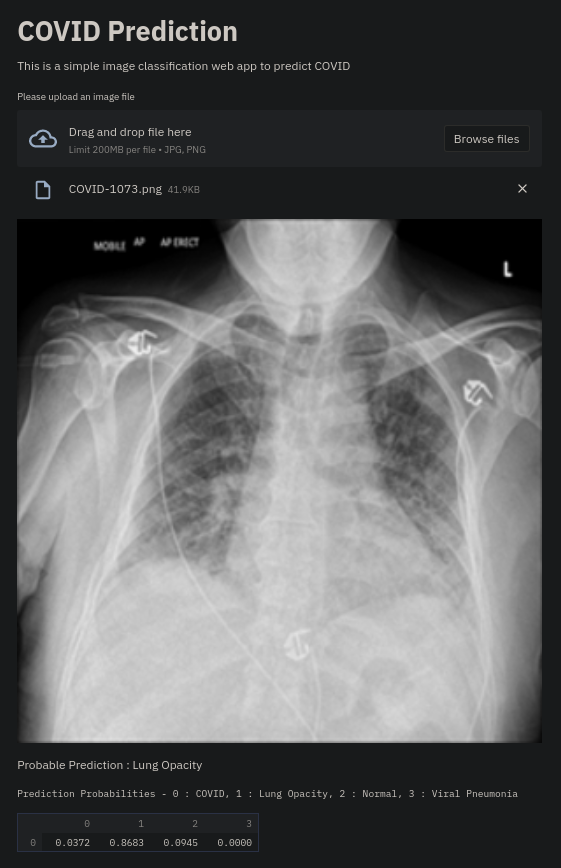

Currently, there is an urgent need for efficient tools to assess the diagnosis of COVID-19 patients. In this project, we propose a constructive solution for detecting and labeling infected tissues on CT lung images of such patients. To cut down false positives our model is trained on 4 types of lung CT images : COVID, Viral Pneumonia, Lung Opacity and normal images to get the best possible results with highest accuracy.

We built it using Tensorflow 2.x using Python. We have developed a Convolutional Neural Network model with an average accuracy of more than 85%. We built the WebApp using Streamlit library for easy interaction with the prediction model.